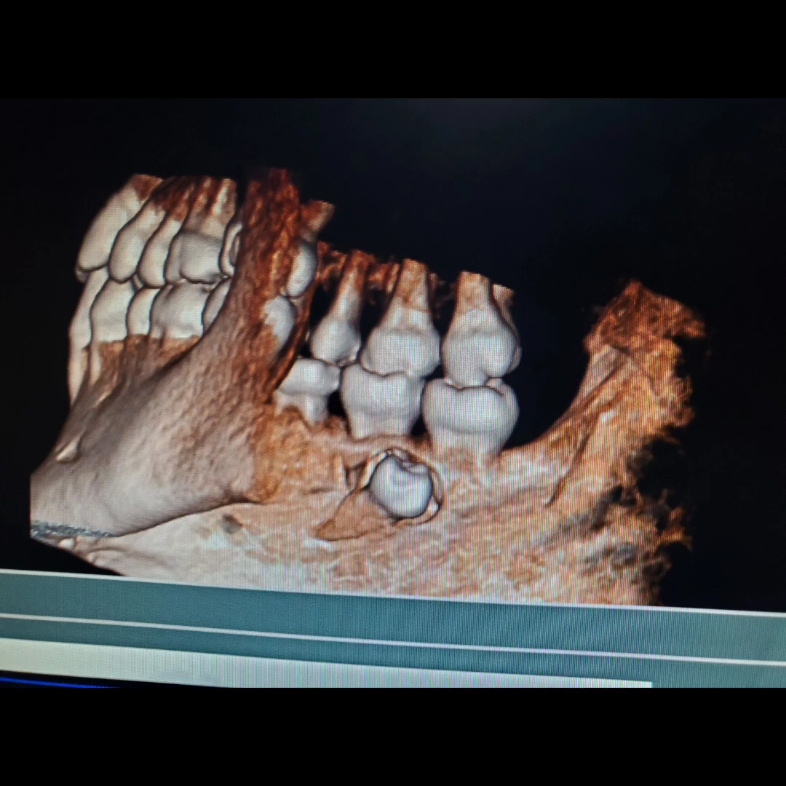

拔横向阻生齿,埋伏牙

图片尺寸1079x809